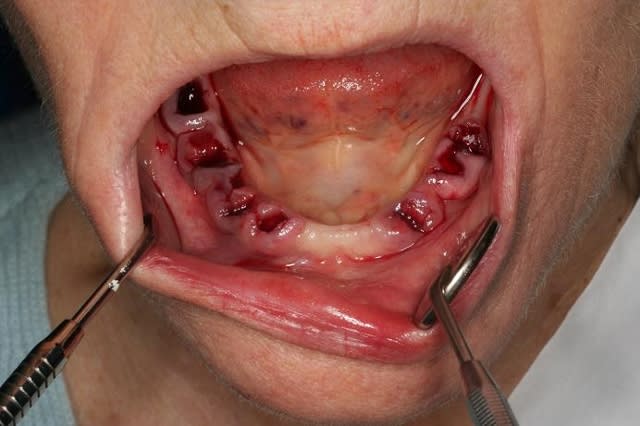

voici un cas extraction, implantation immédiate, mise en charge à 1 jour.

photo1:cas initial paro, mais os résiduel d'un bon volume.

photo3:extractions et curetage alvéolaire++++++

photo 4:pose de 6 implants evl compacts 4/12 (serf). Tous à plus de 45N, sauf en 36...

photo 5: le lendemain, transvissé pret ( on evite 36, pour le laisser tranquille)

photo 6: aspect à 1 jour.

photo 7: transvissé, vissé!

ce fut une grosse matinée, car le curetage fut long et minutieux, ainsi que le modelage des rebords alvéolaires...